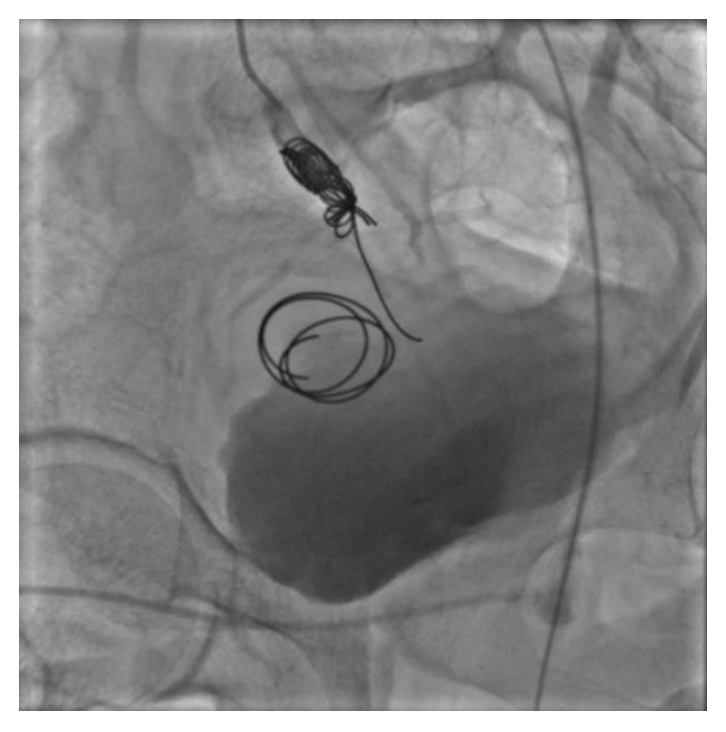

The second patient was a 22-year-old male without medical history, who sustained a knife stab wound to the left buttock 3 months prior to his presentation with disabling pain and paraesthesia in the left lower limb. Physical examination found a pulsatile mass in the lateral left gluteal region. A magnetic resonance angiography (MRA) was performed and confirmed the diagnosis of a pseudoaneurysm in the left gluteal region of 52x94 mm with sciatic nerve reactional inflammation (Figure 5). A cross-over catheterisation of the left femoral artery was performed allowing opacification of the branch of the superior gluteal artery feeding the pseudoaneurysm. An embolization of this branch is done using a 35 Azur detachable coil and two Nester coils of 10 mm (Figure 6). Twenty-four hours later the patient underwent a drainage of the pseudoaneurysm content via a gluteal incision (Figure 7) with good outcome and no residual pain.